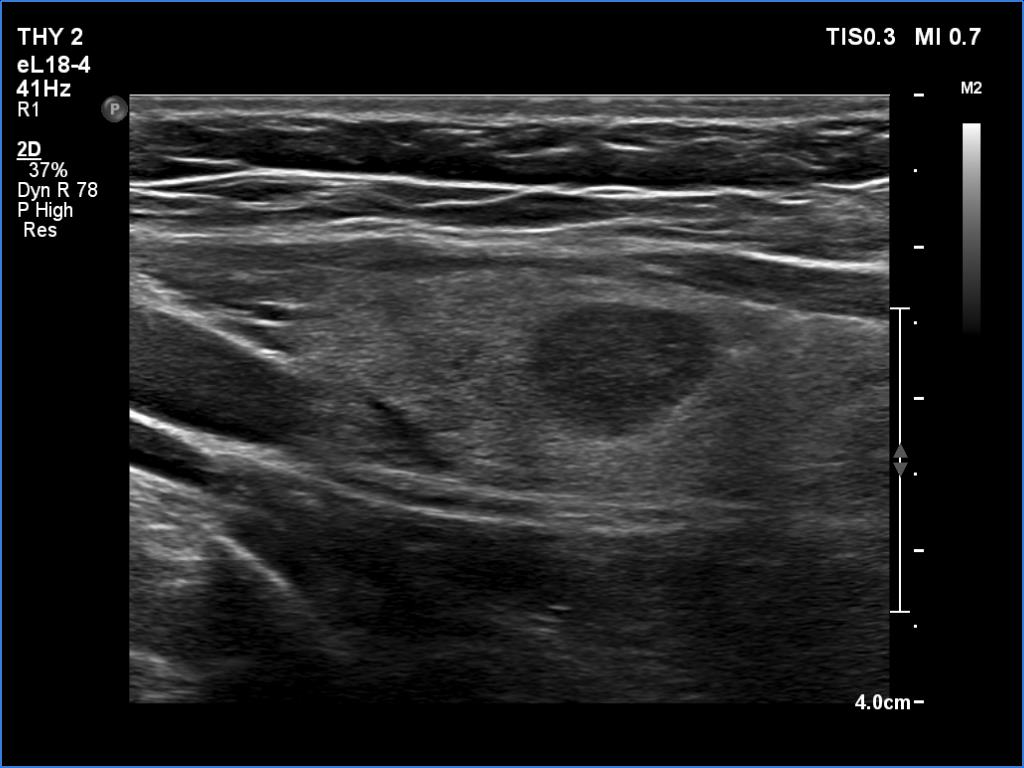

Ultrasonography. The thyroid was echonormal and presented several minimally-moderately hypoechoic areas. One of them, which was located in the central part of the right lobe was deeply hypoechoic and corresponded to pathological nodule. The other lesions seemed to be not true nodules but more active foci of thyroiditis.

Comment. It is worth comparing the deeply hypoechoic nodule with the other discrete lesions. The former has regular, sharp borders, and its echogenicity differs from other areas of the thyroid. These are the main clues of differentiation of a true nodule from a discrete lesion of Hashimoto's thyroiditis.